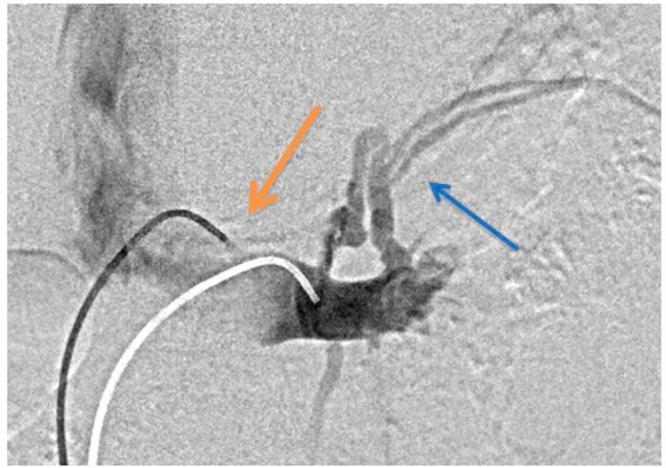

Nutcracker syndrome in adolescent with perineal pain: An interesting case of an adolescent with perineal pain due to pelvic congestion from nutcracker syndrome with relief after balloon venoplasty and sclerotherapy.

Nutcracker phenomenon is the descriptor for a patient's anatomy whenever the left renal vein becomes compressed between the abdominal aorta and the superior mesenteric artery. Nutcracker syndrome is the terminology used when the nutcracker phenomenon is accompanied by symptoms including pain (abdominal, flank, pelvic), hematuria, and orthostatic proteinuria. Diagnosis can be made with Doppler ultrasound, venography, computed tomography, or magnetic resonance imaging. This case demonstrates some of the typical findings of nutcracker syndrome. The limited clinical features and interesting imaging findings, in addition to the young age of the patient, make this a notable case.